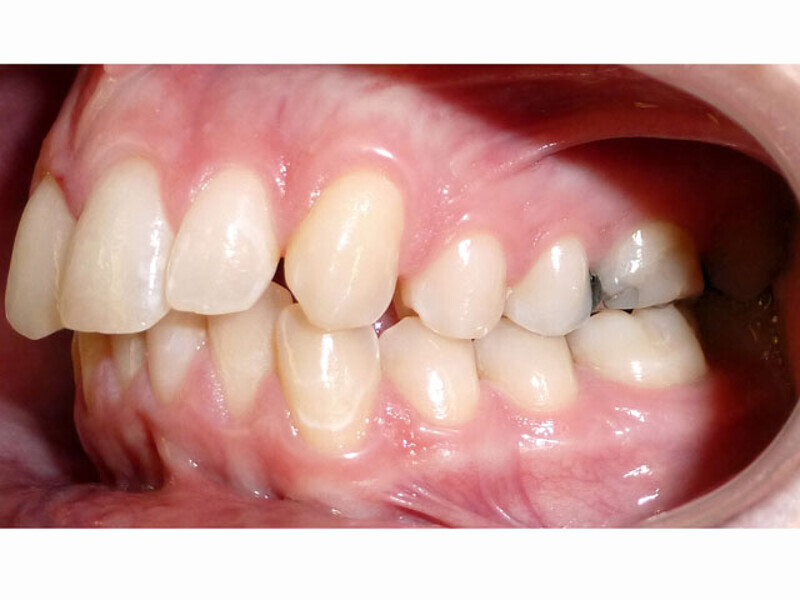

ClearCorrect treatment of crowding